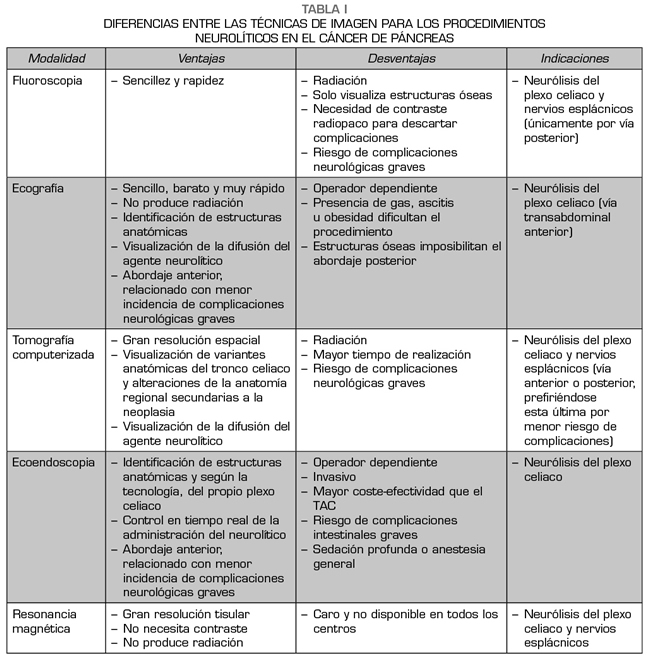

Cada técnica de imagen conlleva unas ventajas, desventajas e indicaciones, que pueden verse resumidas en la Tabla I.